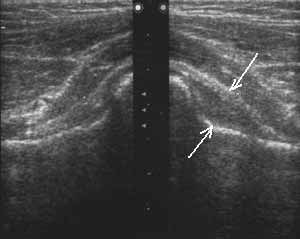

Рис. 2. Сонограммы тазобедренных суставов мальчика 5 лет с коксалгией до начала лечения. Увеличение ультрасонографического суставного пространства на стороне поражения за счет накопления жидкости (синовиит).